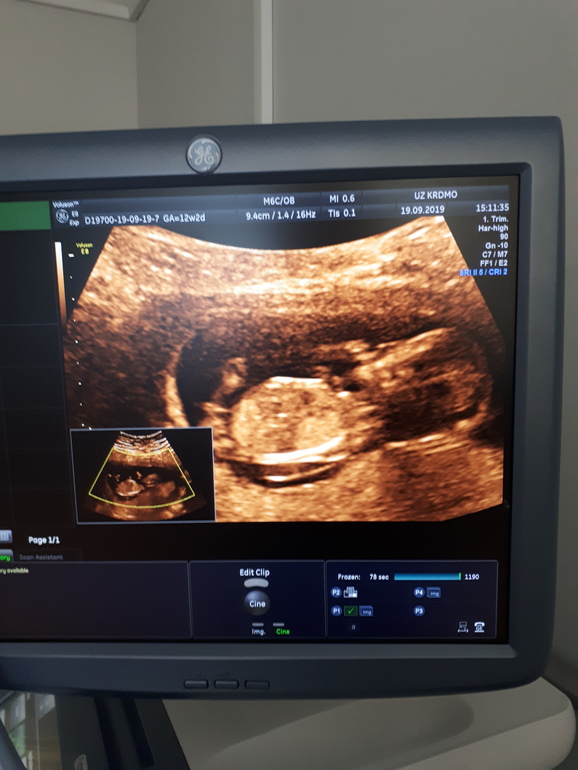

Первый скрининг

Привет!ФУХ! Успокоилась моя нервная система, 3 недели я жила мыслями о сегодняшнем дне. Первый скрининг пройден, моя ляля здорова и развивается по срокам 😍Конечно в бесплатной жк никто мне 3д фотки не печатал, но дали посмотреть как там плавает бубочка, как пальчик сосёт. Приятные новости в конце первого триместра.Осталость отделаться от токсикоза и будет мне счастье.Пойдём через месяц с папой смотреть и узнавать кто там в домике живет,пока на 50% предположили парнишку🤣🤣 50 процентов можно без узи предположить)

Поздравляю Вас!какая красивая картинка😻😭

Обалдеть, там человечек!!! ) Сколько вам неделек?

Какое милое фото!!! Пальчик сосет)))